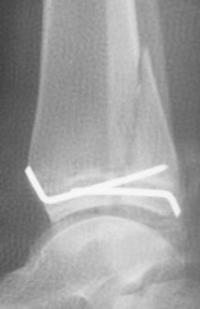

- Traitement :

- En absence de déplacement : immobilisation plâtrée cruro-pédieuse pendant 4 semaines

- En présence de déplacement : réduction anatomique, à foyer ouvert pour contrôle de la réduction et ostéosynthèse par vissage épiphysaire, parallèle au cartilage de croissance

- Reprise de l’appui partiel au déplâtrage avec augmentation progressive de l’appui pour un appui complet à 2-3 mois

- Reprise des activités sportives à 4 mois

- Ablation du matériel vers le 3ième mois pour les broches. En cas d’ostéosynthèse par vis l’ablation du matériel peut être réalisée plus tardivement jusqu’à 6 mois ou 1 an post opératoire.